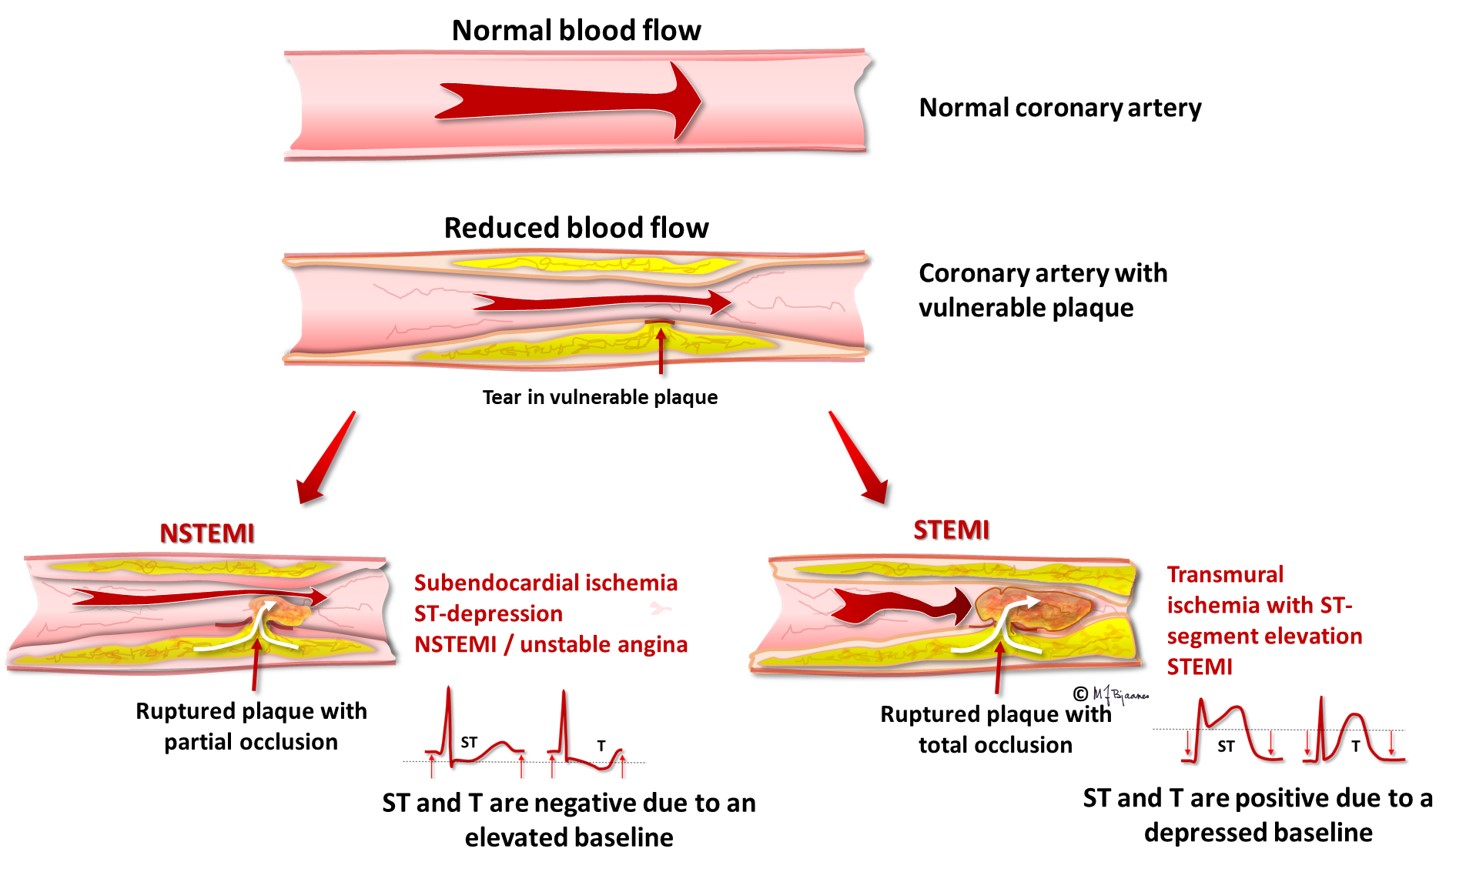

Ischemia is a vascular disease involving an interruption in the arterial blood supply to a tissue organ or extremity that if untreated can lead to tissue death It can be caused by embolism thrombosis of an atherosclerotic artery or trauma Venous problems like venous outflow obstruction and low flow states can cause acute arterial ischemia Ischemia is a condition in which the blood vessels become blocked and blood flow is stopped or reduced When blood flow is diminished to a body part that body part also does not receive adequate oxygen legs critical limb ischemia a form of peripheral artery disease and intestines acute mesenteric ischemia or bowel ischemia

Ischemia is an insufficient supply of blood to an organ usually due to a blocked artery Myocardial ischemia is an intermediate condition in coronary artery disease during which the heart tissue is slowly or suddenly starved of oxygen and other nutrients Ischemia means that there is a reduced blood and oxygen supply to a certain part of the body Locations in the body this condition can affect include the heart intestines brain and limbs Ischemia can happen due to structural or functional problems in the heart but it can have a variety of causes

Ischemic heart disease is heart damage caused by narrowed heart arteries Ischemic heart disease can cause chest pain or discomfort Silent ischemia is when blood flow to the heart is reduced with no obvious symptoms What is myocardial ischemia Myocardial ischemia or cardiac ischemia means your heart muscle is not getting enough blood which contains oxygen and nutrients to work as it should If this lack of blood from your coronary arteries is severe or goes on for more than a few minutes it can damage your heart muscle